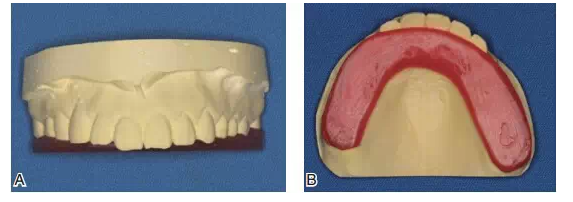

圖10該患者咬合重建修復前的關鍵是先確定牙合平面。A制作馬蹄型蠟板壓在上頜咬合面;B調整蠟板厚度和方向,用牙合平面板確定上頜牙合平面,牙合平面在前牙區(qū)和瞳孔連線平行,在后牙區(qū)和鼻翼耳屏面平行

圖11蠟板所代表的牙合平面

圖12在蠟板下方放置一個石膏平臺

圖13將上頜模型、蠟板、石膏平臺一起上平均值牙合架,取下蠟板后,在蠟板和石膏平臺之間留下的空隙內,用白色嵌體蠟雕刻后牙的牙冠形態(tài),形成恢復上頜正常牙合平面的診斷蠟型